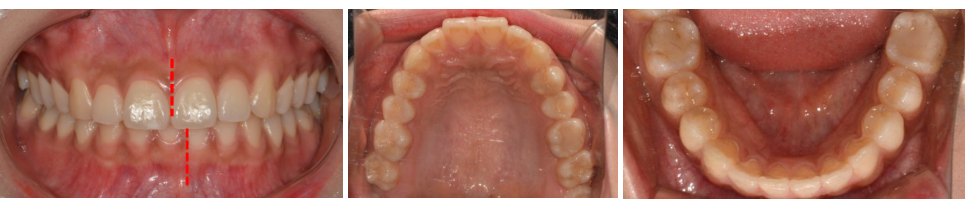

20세 여성, 앞니 돌출 및 웃을 때 비대칭

진단: 편측 치성 2급 부정교합

상하악 치열 중심선 비대칭

상악 전치 돌출, 하악 전치 각도 양호

좌측 어금니 교합 어긋남, 우측 비교적 안정적